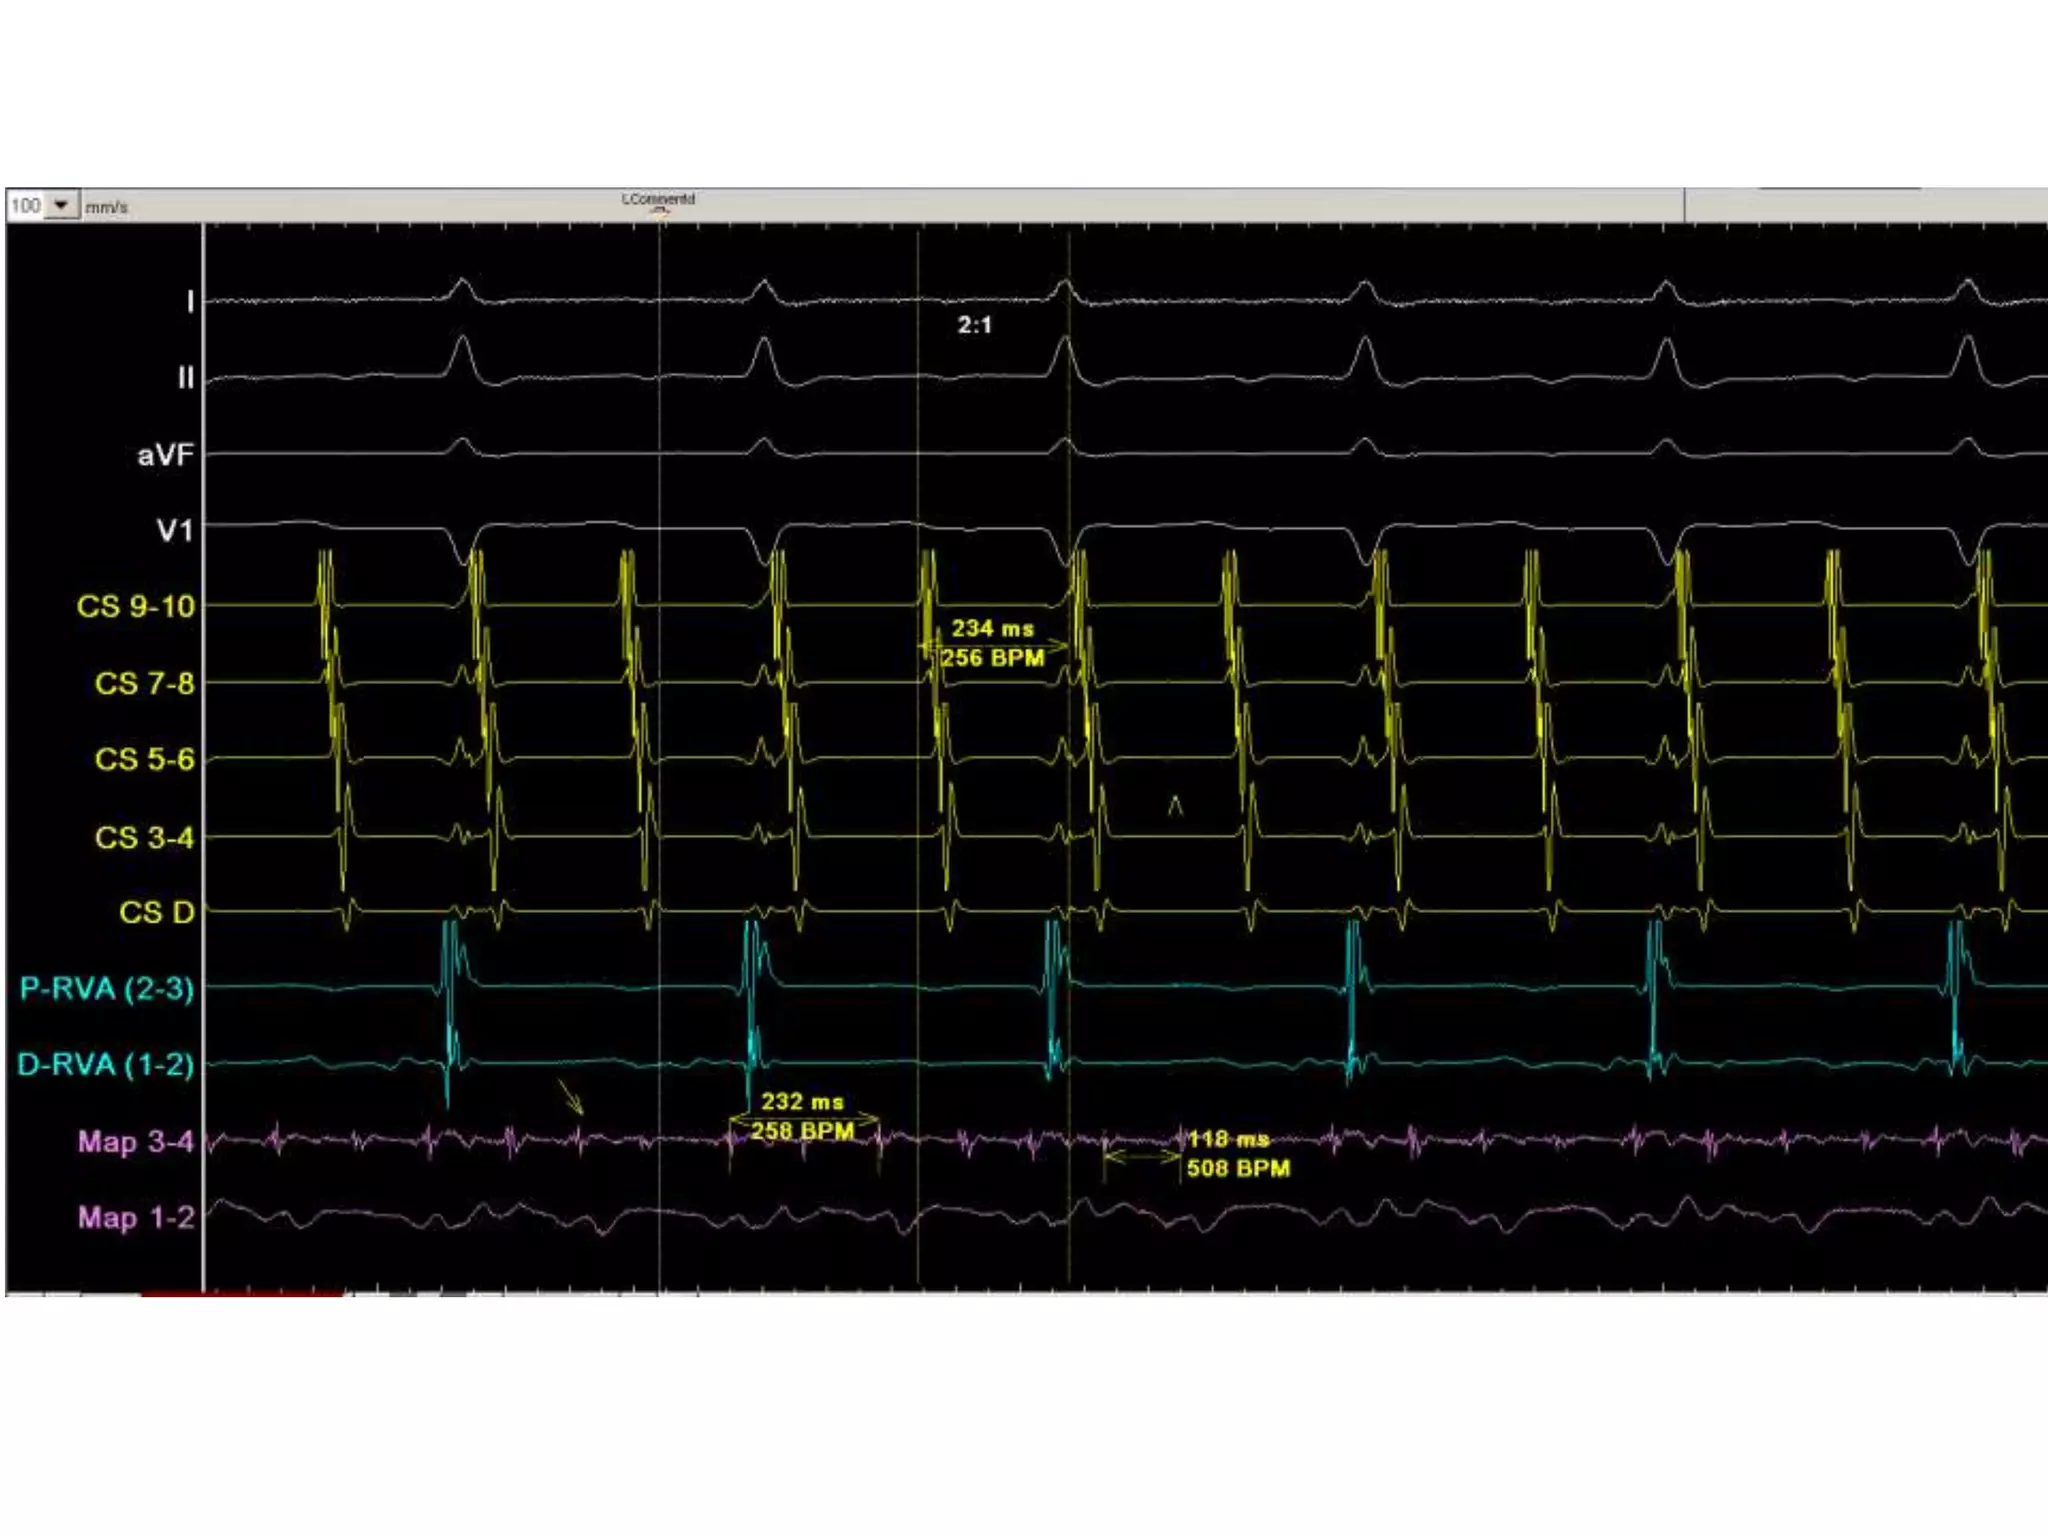

Le flutter commun est une arythmie fréquente dont l'origine est l'oreillette droite Le flutter auriculaire (flutter) est un trouble du rythme fréquent, généralement associé à une cardiopathie structurelle et à une fibrillation auriculaire (FA) Le flutter auriculaire lent, bien tolérée et survenant chez un sujet âgé sans maladie cardiaque, n'est pas une indication de réduction par choc électrique mais peut constituer une parfaite indication pour la réalisation d'une ablation par radiofréquence.

Ablation du flutter rythmologiepitie. Le flutter auriculaire lent, bien tolérée et survenant chez un sujet âgé sans maladie cardiaque, n'est pas une indication de réduction par choc électrique mais peut constituer une parfaite indication pour la réalisation d'une ablation par radiofréquence. Nous aborderons également le traitement aigu et la thérapie interventionnelle

ablation du flutter du coeur ablation flutter cardiaque Bollbing. Après avoir introduit des cathéters dans la veine fémorale, l'isthme cavo tricuspide est ciblé L'explication physiopathologique courante est une réaction inflammatoire auto-immune à l'intérieur de l'espace péricardique liée à des anticorps anti-cœur secondaires à une lésion myocardique.